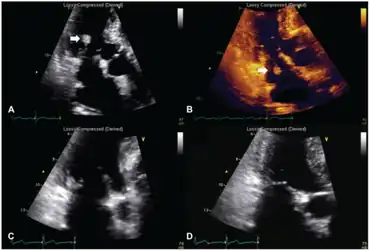

| a,b) Transthoracic echocardiography - NBTE arrow c.d) after anticoagulation therapy lesion practically disappeared | |